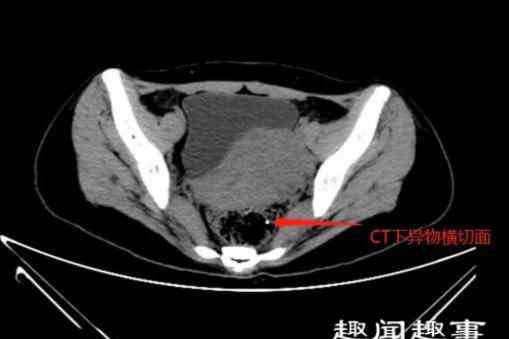

住院安排办好以后,尹医生马上安排了直肠肛管彩超及盆底CT以进一步明确异物的位置及大小。其中盆底CT显示,异物已穿破直肠壁层。

但是手术过程中,并没有看见异物,尹医生再次凭借B超及CT检查,判定异物垂直插入直肠下段,并穿破直肠壁,进入粘膜下层的位置,最后在切开部分直肠下段粘膜,在距离肛管2厘米处,找到了一米白色异物尾端,予取出。